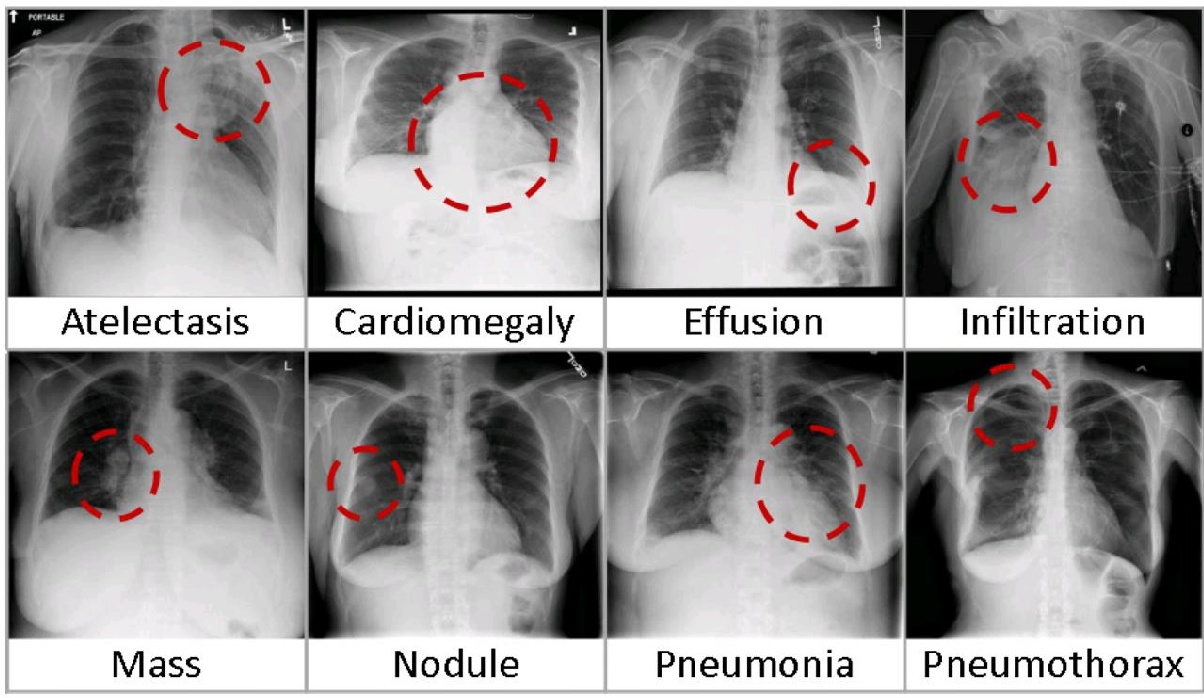

• b. Radiological imaging diagnostics